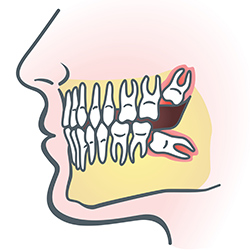

Wisdom teeth

Wisdom teeth are molars found in the very back of your mouth. They usually appear in late teens or early twenties, but they may become impacted (fail to erupt) due to lack of room in the jaw or angle of entry. When a wisdom tooth is impacted, it may need to be removed. If it is not removed, you may develop gum tenderness, swelling, or even severe pain. Impacted wisdom teeth that are partially or fully erupted tend to be quite difficult to clean and are susceptible to tooth decay, recurring infections, and even gum disease.

Wisdom teeth are typically removed in the late teens or early twenties because there is a greater chance that the roots have not fully formed and the bone surrounding the teeth is less dense. These two factors can make extraction easier as well as shorten the recovery time.

In order to remove a wisdom tooth, your dentist first needs to numb the area around the tooth with a local anesthetic. Since the impacted tooth may still be under the gums and embedded in your jaw bone, your dentist will need to remove a portion of the covering bone to extract the tooth. In order to minimize the amount of bone that is removed with the tooth, your dentist will often "section" your wisdom tooth so that each piece can be removed through a small opening in the bone.

Once your wisdom teeth have been extracted, the healing process begins. Depending on the degree of difficulty related to the extraction, healing time varies. Your dentist will share with you what to expect and provide instructions for a comfortable, efficient healing process.